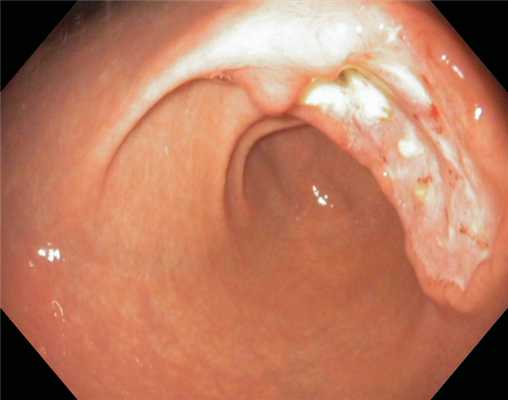

ВРВ пищевода после эпизода кровотечения. Тромбированная вена - тромб белого цвета..

Пациент с циррозом печени и портальной гипертензией.